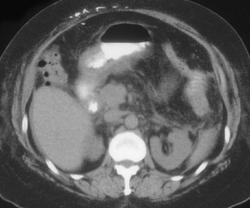

Gastrocolic Fistulae Secondary to Colon Cancer